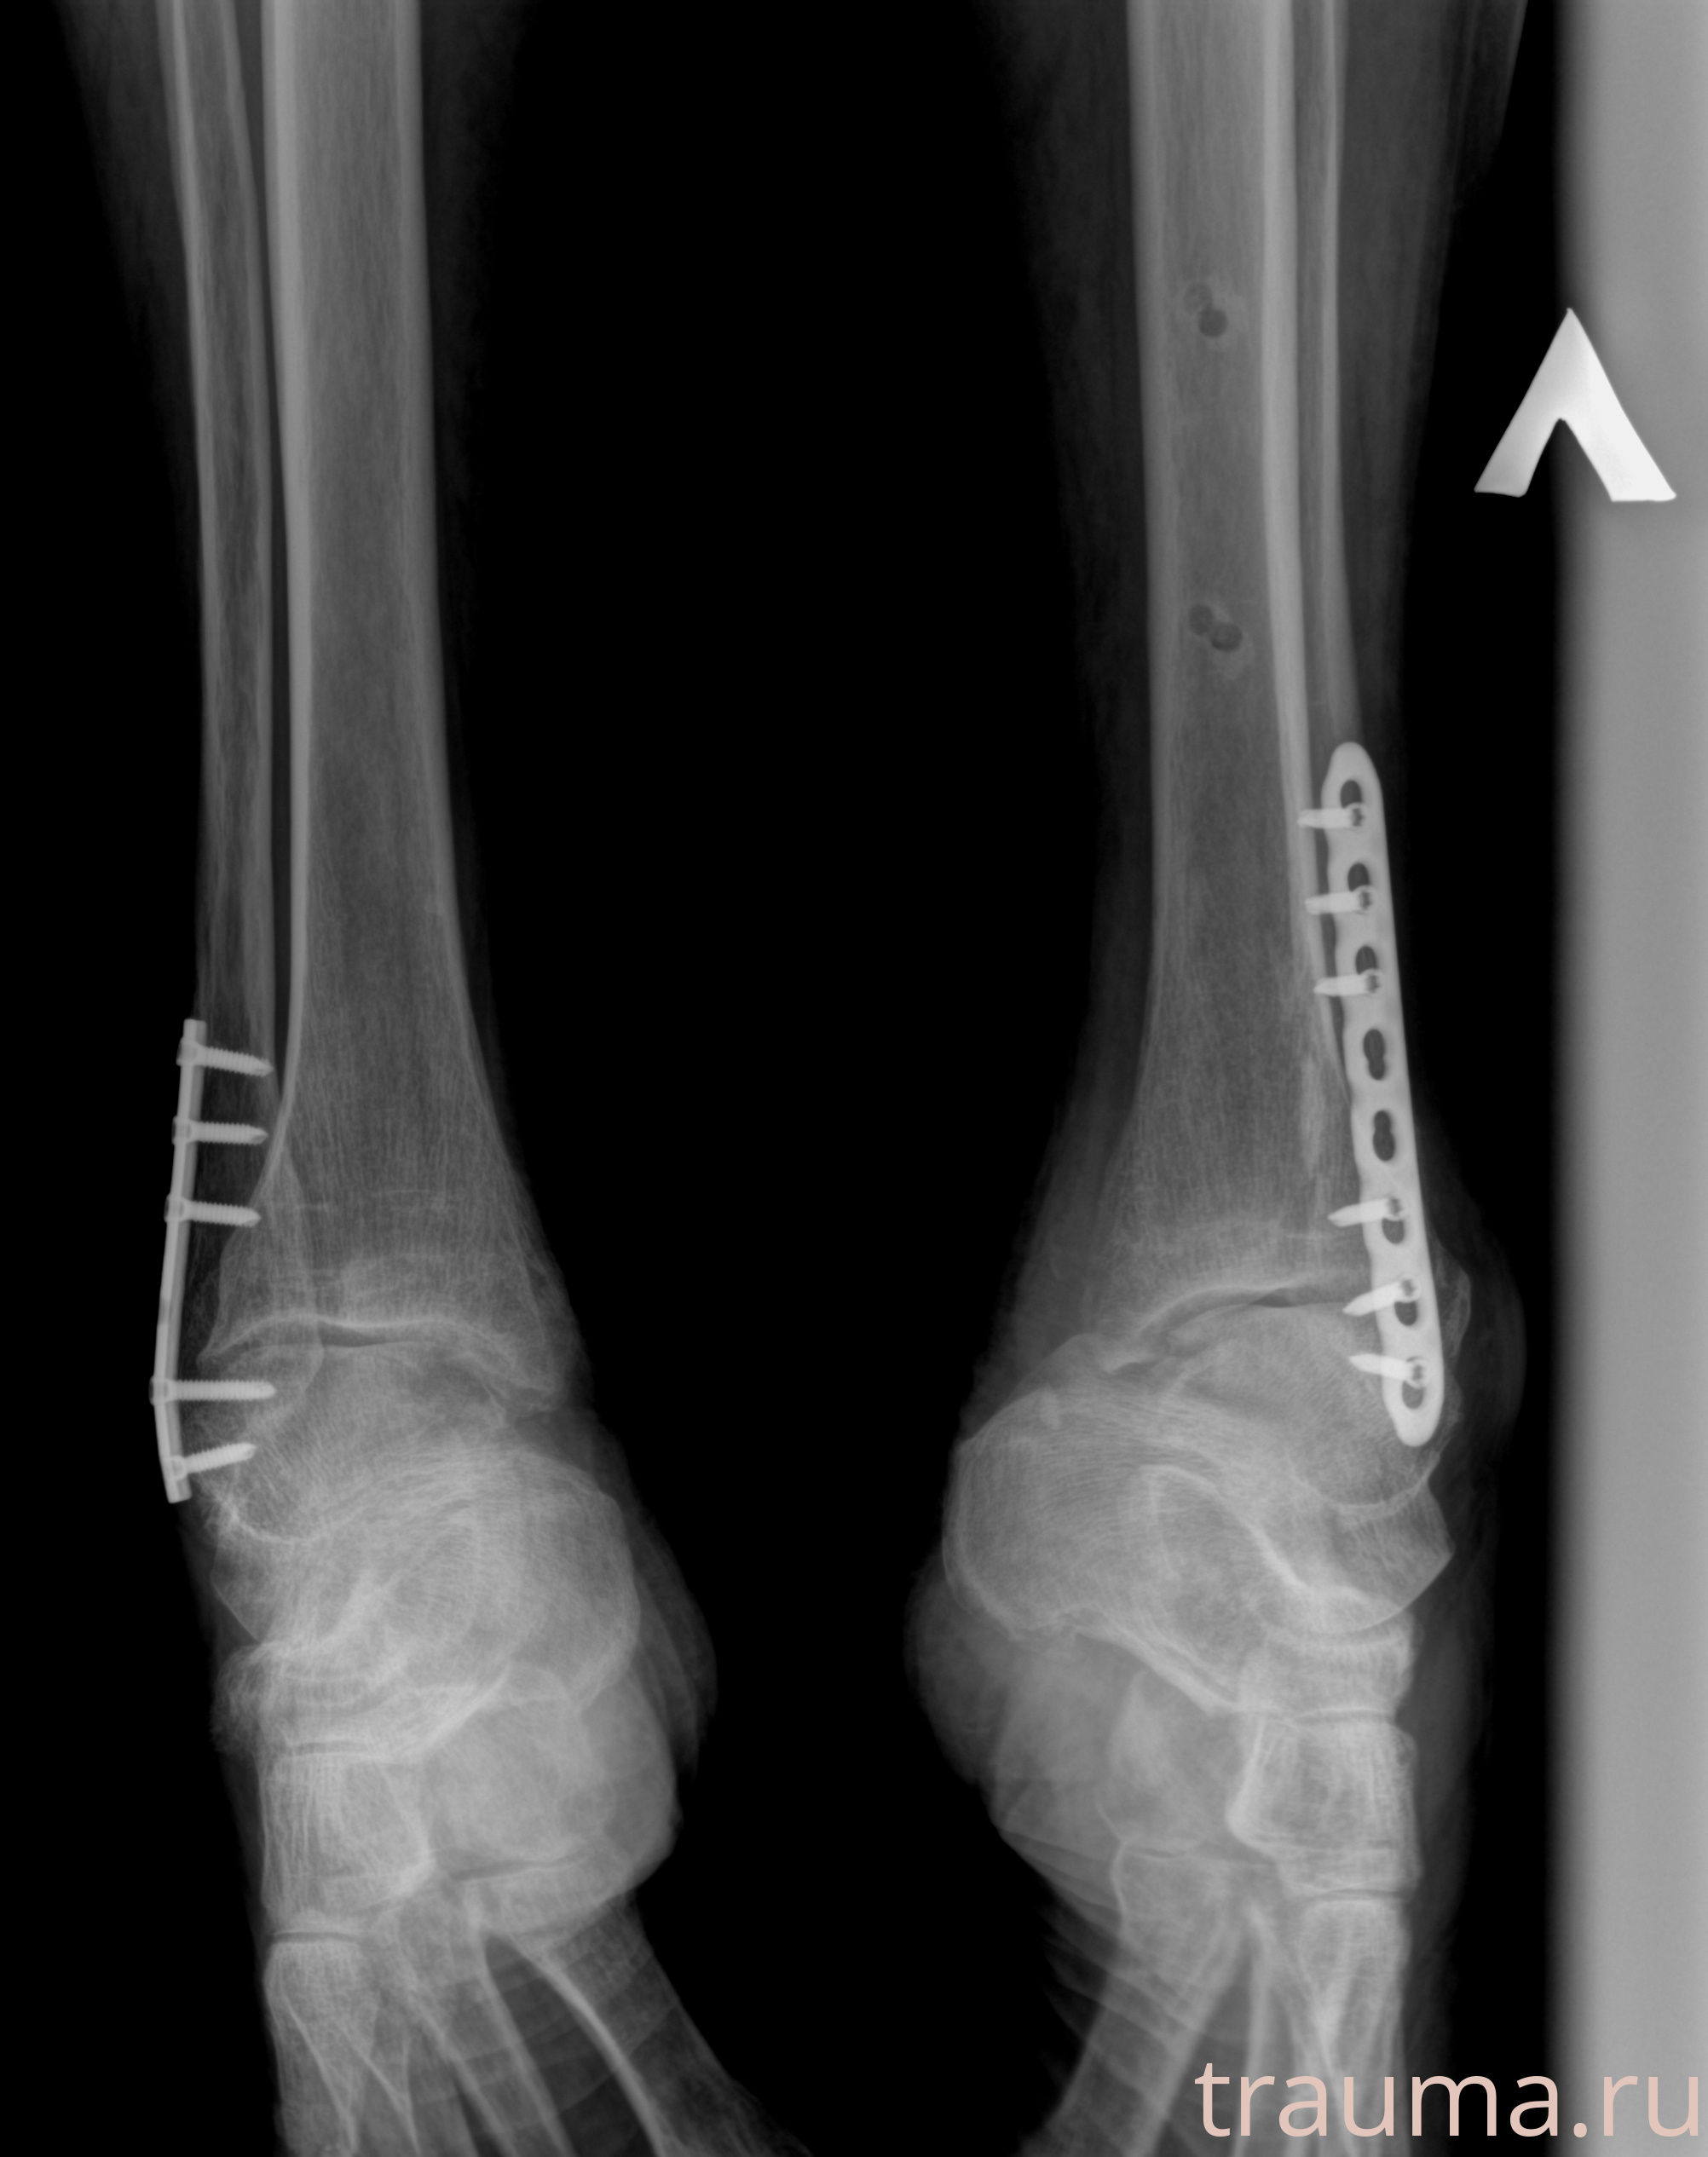

Рентгенограммы